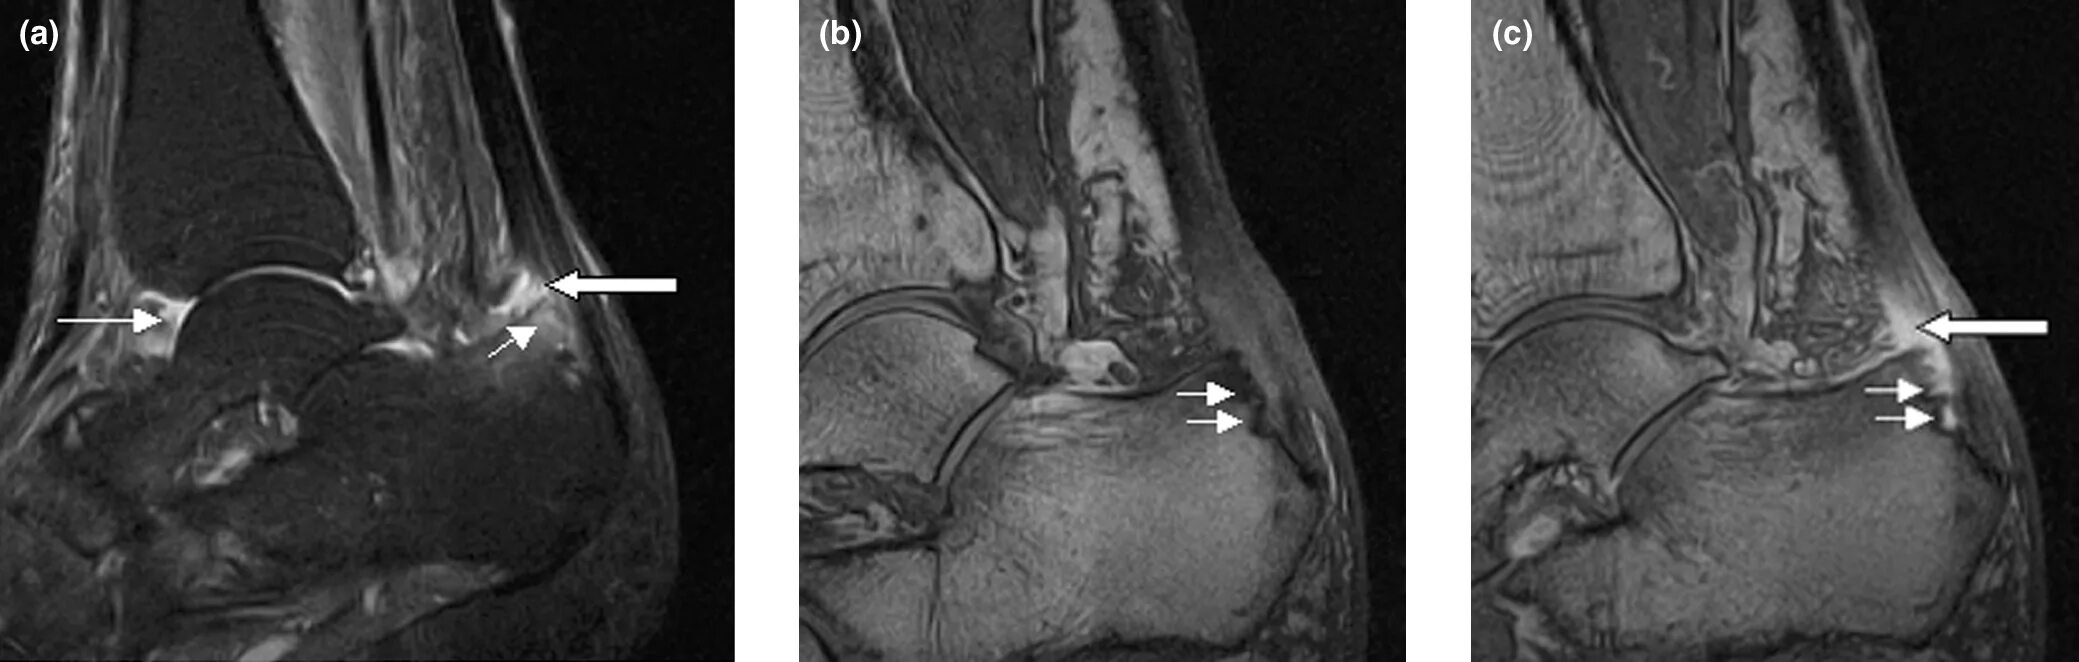

Синовит голеностопного таранного сустава